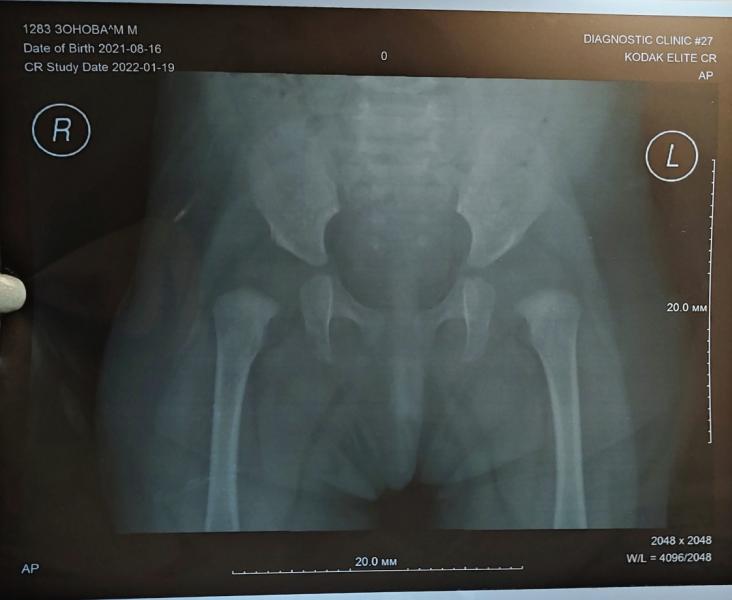

Дисплазия. Много ли вы знаете о ней? Или так же, как и я, думали,что самое ужасное это то,что ядрышки еще не сформировались. В общем виновата отчасти сама, отчасти виню ортопеда в пк, который толком ничего не объяснил и пришлось на интуитивном уровне разбираться самой. В итоге сходили к двум лучшим ортопедам города Новосибирска Мацук и Семенов. Они назначили шины, но только разные, один назначил шину Виленского, другой шину орлетт, один назначил только шину, второй назначил кучу физио лечения,массажи. Диагноз у одного дисплазия,но тяжелая,у другого подвывихи, оба говорят,что все серьезно. Но и это не всё, написала я в институт Турнера в Питере, ответил Волошин - оперирующий врач ортопед (кто в теме, тот поймет). И он отметает все лечение, говорит нужна совсем другая шина, говорит прилетайте в ближайшее время, нужен очный осмотр, изготовление индивмдуальной шины, все очень серьезно. А вот прям сорваться в Питер мне сложно, и в финансовом плане и морально я не готова одна лететь, нужно с мужем, у него работа и у нас старшая дочь еще, даже в сад не ходит. Но это, конечно, решаемо, но не прям по щелчку пальцев и думаю надо ли ехать или верить нашим вопчам. Я вообще не знаю что делать, читаю, что всех этих врачей очень хвалят, но каждый из них опровергает лечение другого, у меня в голове такая каша, я перелопатила интернет в поисках информации о дисплазии, я даже научилась читать рентгеновские снимки и поняла что к чему. Но кому верить из врачей - не знаю. Мы очень поздно начали лечение и упускать время нельзя. Может кто-то сталкивался с такой проблемой, может кто-то поделится своим опытом, даст контакты ещё одного хорошего врача.

Вы, видимо, тоже не до конца разобрались с вопросом о дисплазии. Дисплазия это как раз и есть то, что сустав не сформирован, сформирован неправильно. Если слева сустав не совсем на месте, то это может быть подвывих и это уже серьезно. Вам делали рентген? В три месяца,говорят, уже подушка Фрейка не актуальна, нужна другая шина. Но! Шину носить обязательно. Мы пренебрегали, как и вы шиной фрейка,потому что неудобно. Теперь я жалею об этом.